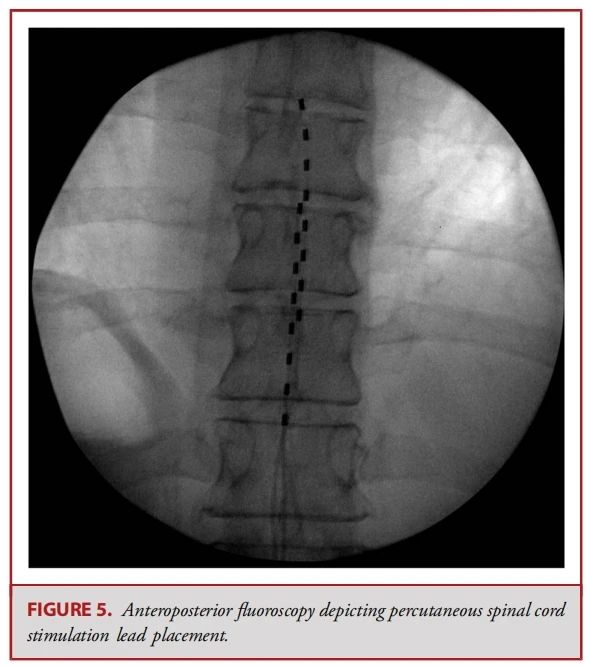

● 经皮电极通常由 8 个球形接触点组成,而鳍状电极则通常具有16至20个接触点,且所有接触点都平铺在硬膜表面(见图 1-3)。经皮电极通常通过改良版的 Tuohy 导管进行插入(见图 4)。在使用失去阻力法进入硬膜外腔后,电极在透视引导下被推进至与疼痛部位相应的脊髓节段(见图 5)。经皮电极和鳍状电极在镇痛效果上具有相似的疗效。经皮电极植入属于较低侵入性的手术,术后并发症的发生率较低(2.2%,相较于鳍状电极3.4%),因此对于合并症较多的患者来说,是一种更为理想的选择。鳍状电极虽然更具侵入性,但与圆柱形经皮电极相比,电极移位的发生频率较低。由于鳍状电极具有更多接触点,因此可以实现更为精准和高效的刺激。